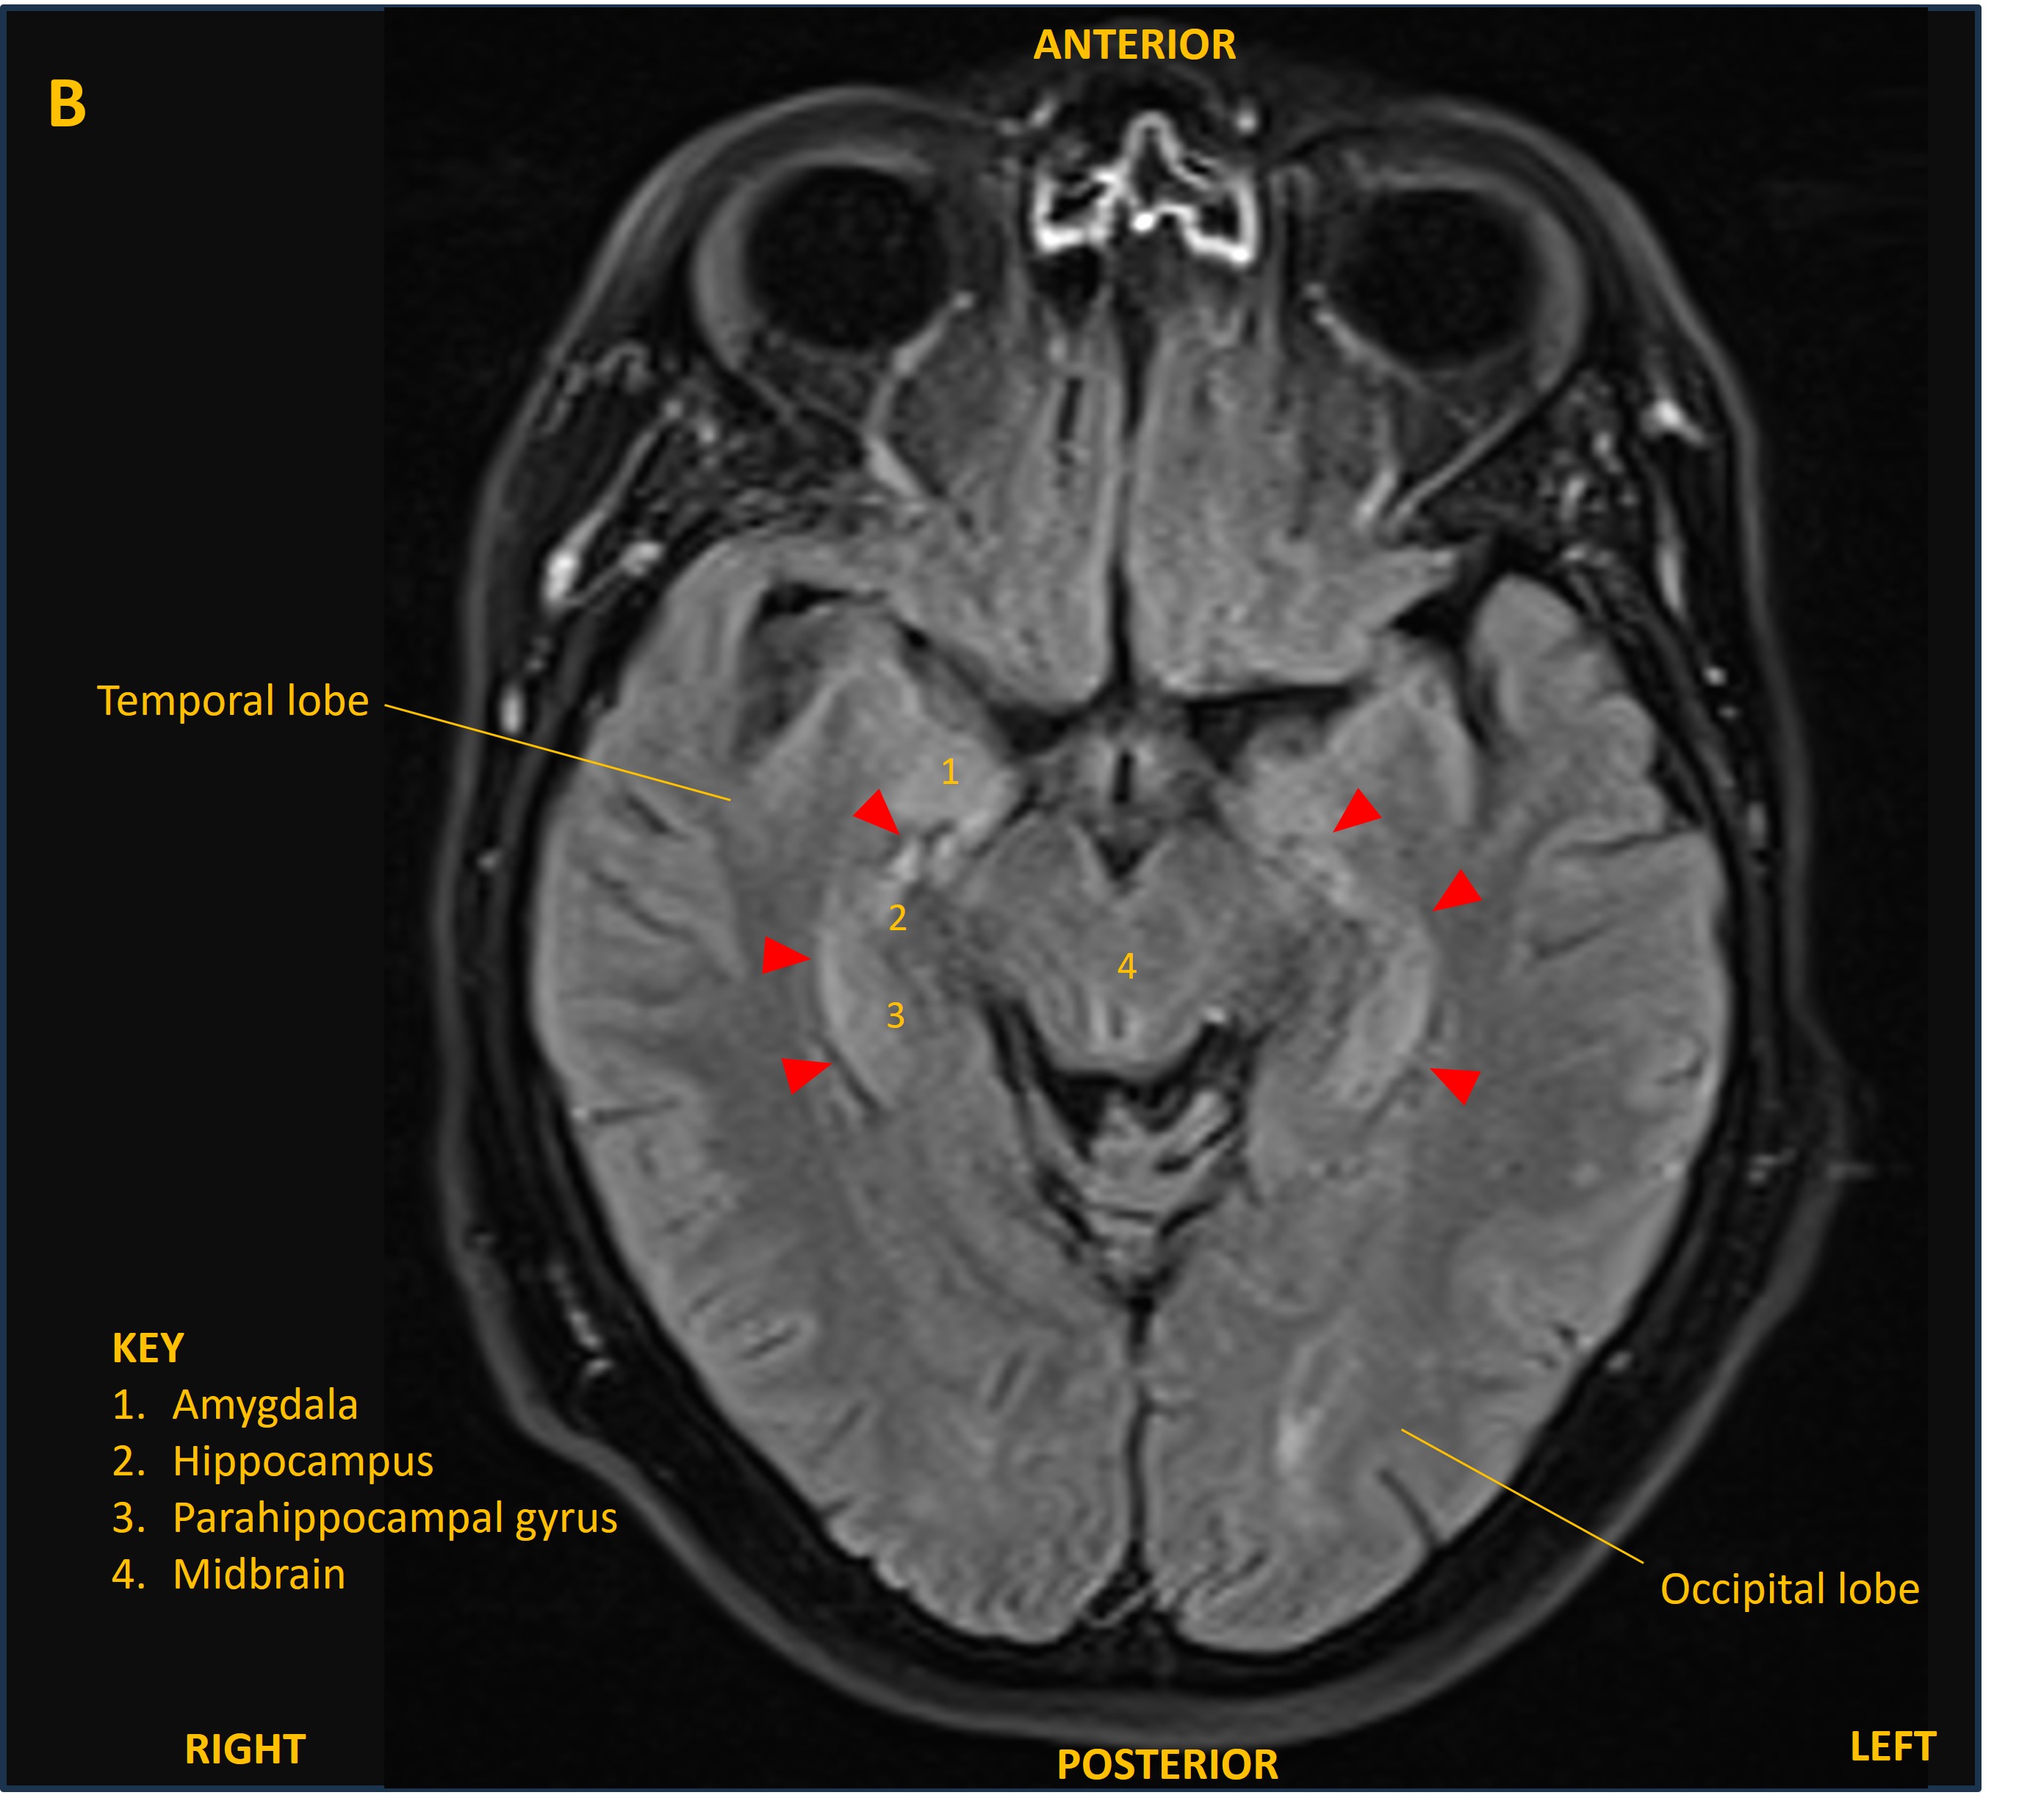

The patient was admitted and was treated empirically with aciclovir for possible viral encephalitis until a lumbar puncture showed normal CSF cell counts, glucose, and protein, and viral PCR was negative. An MRI brain showed bilateral changes on FLAIR confined to the mesial temporal lobes, involving the hippocampi and other limbic structures (figure A and B, red arrowheads). This was suggestive of limbic encephalitis.

MRI B